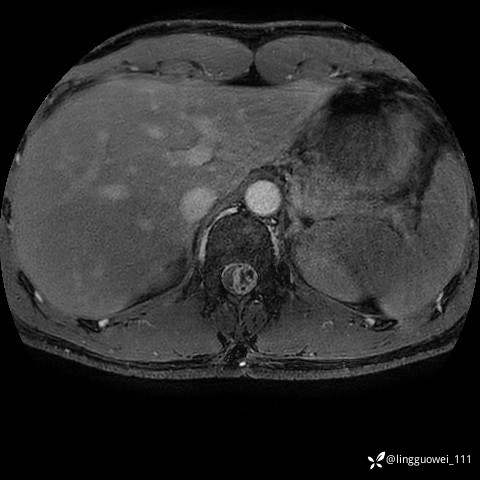

男,38岁,反复腰痛伴双腹股沟区痹痛半年,加重1月。

腰椎MR,注意脊髓异常信号,与伪影鉴别,一不小心就会漏诊

T2WI T2WI+FS